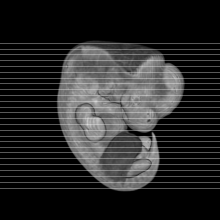

MRI Slice Selector

Mouse: click on a line below to select a view

Finger: tap a line below with a very light touch